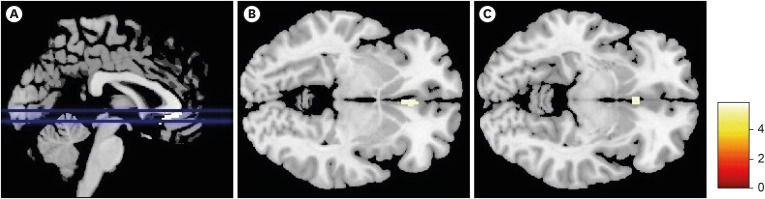

Methods: We evaluated the brain MRI data from 87 TGA patients and 20 age- and sex-matched control subjects. We included brain MRIs obtained from TGA patients within 72 hours of symptom onset to verify the pre-existence of structural change. For voxel-based morphometric analyses, statistical parametric mapping was employed to analyze the structural differences between patients with TGA and control subjects.

Results: TGA patients exhibited significant volume reductions in the bilateral ventral anterior cingulate cortices (corrected p<0.05).

Conclusions: TGA patients might have pre-existing structural changes in bilateral ventral anterior cingulate cortices prior to TGA attacks.